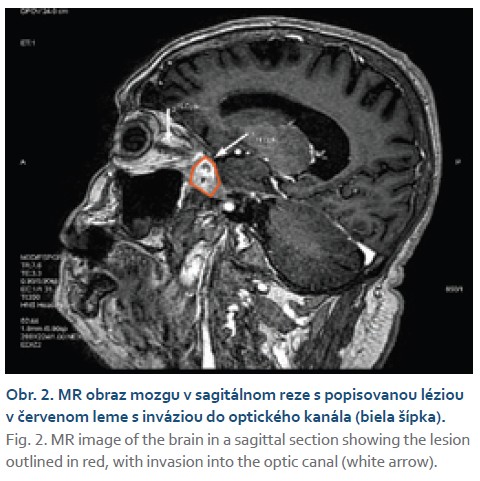

V marci roku 2023 bol pacient odoslaný na Hepatologicko-gastroenterologické a transplantačné oddelenie (HEGITO) vo FNsP F. D. Roosevelta v Banskej Bystrici za účelom doriešenia stavu. U pacienta naďalej pretrvávali bolesti hlavy skôr epizodického charakteru najmä v noci a pár dní pred hospitalizáciou došlo u pacienta opätovne k strate vízu na pravom oku. V úvode hospitalizácie sme u pacienta v akútnom režime doplnili kontrastné CT mozgu, kde bola popisovaná sýtiaca sa lézia o veľkosti 20 × 13 mm lokalizovaná na alla major ossis sphenoidalis l.dx s pokračovaním do orbity do canalis opticus l.dx, kde čiastočne zavzala dorzálnu 1/4 nervus opticus. Následne ešte doplnené MR mozgu potvrdilo uvedenú léziu so zavzatým nervus opticus a čiastočne aj musculus rectus orbit melis. Na základe zobrazovacích metód sa rádiológovia prikláňali k ­gnóze suspektného tumoru vs. meningeómu, menej pravdepodobná bola možnosť abscesového ložiska (obr. 1, 2).

V rýchlom slede sme počas hospitalizácie zrealizovali oftalmologické konzílium, ktoré potvrdilo amaurózu na pravom oku a edém papily terča zrakového nervu. Konzultovaný neurológ odporučil zahájiť antiedémovú a analgetickú liečbu, doplniť neurochirurgické konzílium.Vzhľadom na nevylúčenú možnosť infekcie sme súbežne empiricky zahájili aj antibio­tickú a antimykotickú liečbu (amfotericín B). ORL konzílium vylúčilo prítomnosť fokusu v prínosových dutinách. Kompletné serologické vyšetrenie vrátane vyšetrenia galaktomananu bolo u pacienta negatívne. Po dohovore s neurochirugom sme doplnili ešte MR spektroskopiu, ktorá vyslovila podozrenie na abscesové ložisko s postihnutím leptomeningov. Vzhľadom na daný nález bol pacient indikovaný na odber histologickej vzorky z popisovaného ložiska na Neurochirugickom oddelení. Po obdržaní histologického výsledku sme stav definitívne uzatvorili ako mykotickú infekciu mozgu spôsobenú Aspergillus spp. (obr. 3).